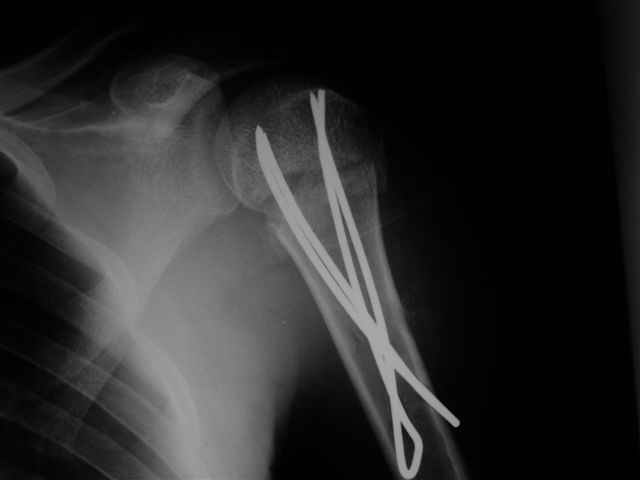

Здесь случай перелома-вывиха плеча, больному 56 лет, после "дважды" закрытой неудачной репозиции, опять же ургентно взяли в операционную, после полного общего обезболивания попытались сделать репозицию, и фиксацию провели спицами.

Больной находился в повязке, примерно напоминяющей косыночную, рекомендованы движения в локтевом суставе и маятниковые движения в плече, спицы удалены в три недели (были случаи миграции)

Больной амбулаторный, предупрежден на случай осложнения АВН головки.

сделать закрытую репозицию с помощью ЭОПа совсем не сложно, после этого еще проще провести 3-6 спиц и получить красивую рентгенограмму. Есть только небольшая проблема это ROTATOR CUFF. Для плечевого сустава только костное восстановление не достаточно. для функции плечевого сустава нужны вращатели.

Давайте представим себе состояние манжетки вращателей после вывиха плеча, а еще и с отрывным переломом бугров. Головка может и прирастет, еесли не будет аваскулярного некроза, но хорошего функционального результата не ждите.

Висеть будет красиво. У людей физически активного периода жизни нужно открыть, восстановить костную анатомию и восстановить сухожильный аппарат.

В этом плане Locking plate очень хороша так как позволяет начать движения сразу после операции.

Клинические снимки - 3 недели после операции

с уважением М. Беренштейн